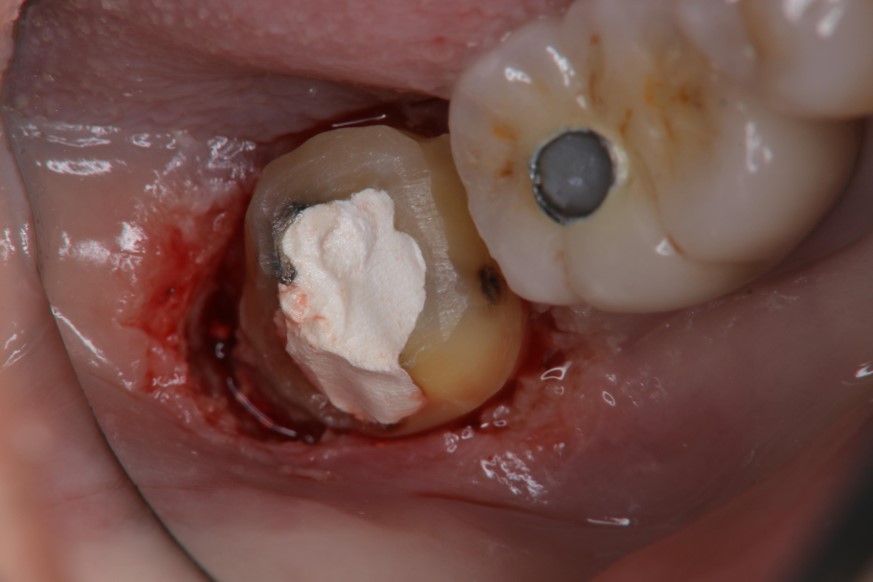

水雷射牙冠增長手術

膺復前評估牙齦、牙齒狀態